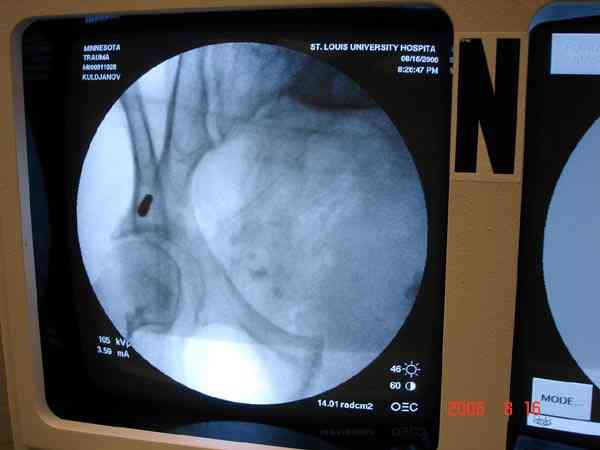

Примерно такой фиксатор наложил вчера ночью, но патология была экстренная травма: больному 53 года, поступил после мотоциклетной травмы, черепно-мозговой, абдоминальной, челюстно лицевой с потерей одного глаза, сосудистой и из скелета перелом крестца слева с диастазом симфиза и множественные переломы ребер.

Здесь соблюдался алгоритм больному с внутритазовым кроветечением после нестабильного перелома таза.

Обычно поступившим в приемное отделение больным с переломами конечностей, полученным в результате автоаварии или результате других скоростных травм по протоколу проводятся исследования на КТ ургентно. Череп всем бессознательным больным и живот при подозрении на внутреннее кровотечение.

Шоковым с повреждением таза, перед КТ исследованем накладывается антишоковые трусы.

Для стабилизации перелома и кровопотери, сперва была попытка наложения простыни вокруг таза для уменшения объема таза. Для оперативного доступа в области живота и передней части таза простыню заменили на Beam Bag (матрац который после удалении воздуха принимает контуры тела).

Одновременно с хирургами, которые занялись ксплоративной лапаротомией, мы приступили к фиксации временным аппаратом для уменьшения диастаза симфиза. После установки аппарата удалось стабилизировать давление, потом наше место занял сосудистый хирург, который нашел кровоточащую левую артерию epigastrica. Кровоточаший сосуд затромбизировал эндоваскулярно введением 4 coil placement.

Много кровепотери было из лицевых ран. Кроме забрюшинной гематомы, крови накопилось в абдоминальной части между мышечными стенками и под кожей. Кровопотерю заместили более 20 доз препаратов крови и INR опустился изначалнего 9.5 до 1.0 в конце. Находится в реанимации, стабильный, надеемся через несколько дней займемся окончательной фиксацией переломов костей таза.